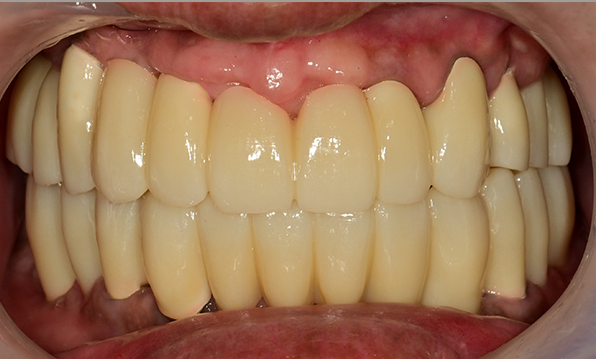

Case 02

Before After